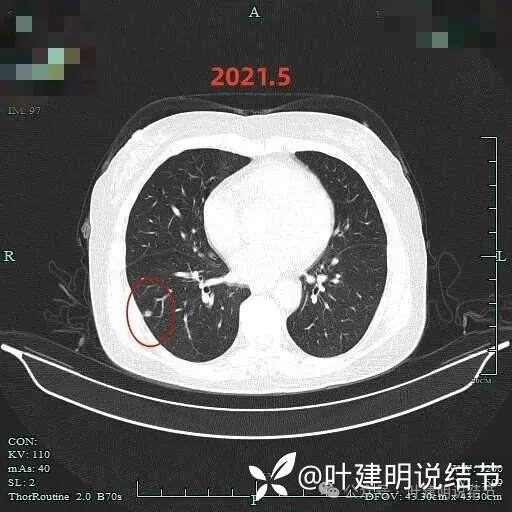

到了2021年5月右下病灶是2毫米层厚的了,显得密度略高,表面毛糙,离胸膜近。